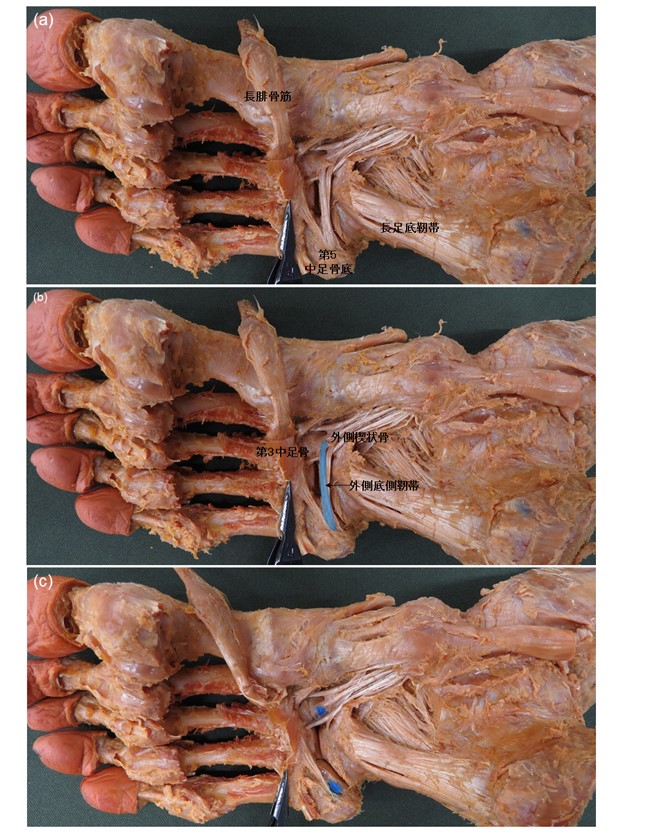

その結果、外側底側靭帯は3つのタイプに分類でき、出現率は62%でした。先行研究では第5中足骨底から第2中足骨を結ぶ靭帯であると報告されていましたが、本研究の結果では、100足中99足で第5中足骨底と外側楔状骨を結ぶ靭帯として観察できました。また、長さは約32mm、幅は約2.3mm、厚さは約0.2㎜であり、非常に薄い靭帯であることが明らかとなりました。この靱帯だけではアーチの剛性にあまり寄与しない可能性が考えられました。しかし、外側底側靭帯は高い確率(85%)で隣接する長足底靭帯や後脛骨筋腱と結合していたため、これらの組織と連結して足部の剛性に寄与している可能性が考えられました。

TypeⅠ:帯状の外側底側靭帯が存在している

TypeⅡ:外側底側靭帯が長足底靭帯や後脛骨筋腱と連結している

TypeⅢ:外側底側靭帯が欠損している

1:外側底側靭帯,2:長足底靭帯と連結する線維束,3:長足底靭帯,4:後脛骨筋腱と連結する線維束,5:後脛骨筋腱,6:底側靭帯(内側楔状骨-第2・3中足骨間),7:長足底靭帯と後脛骨筋腱と連結する外側底側靭帯